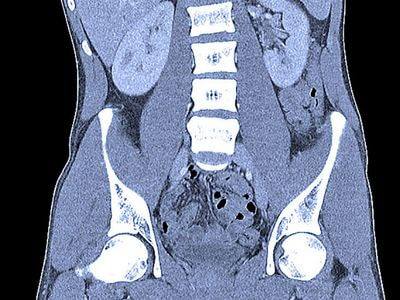

КТ дуже корисна для виявлення захворювань сечостатевої системи, оскільки вона надає детальні зображення органів і структур в цій області тіла. Зокрема, за допомогою КТ можна виявити патології в нирках, сечовому міхурі, передміхуровій залозі, яєчках і матці.

КТ часто використовується для виявлення захворювань нирок, таких як камені в нирках, кісти та пухлини. Зображення, отримані за допомогою КТ, можуть виявити розмір, розташування та форму будь-яких аномальних утворень у нирках. Ця інформація може допомогти лікарям визначити відповідне лікування, наприклад, хірургічне втручання або променеву терапію.

КТ також може виявити захворювання сечового міхура, такі як камені в сечовому міхурі, інфекції та пухлини. Ці сканування можуть виявити розмір, розташування і форму будь-яких аномальних утворень у сечовому міхурі. Ця інформація може допомогти лікарям визначити відповідне лікування, наприклад, хірургічне втручання або хіміотерапію.